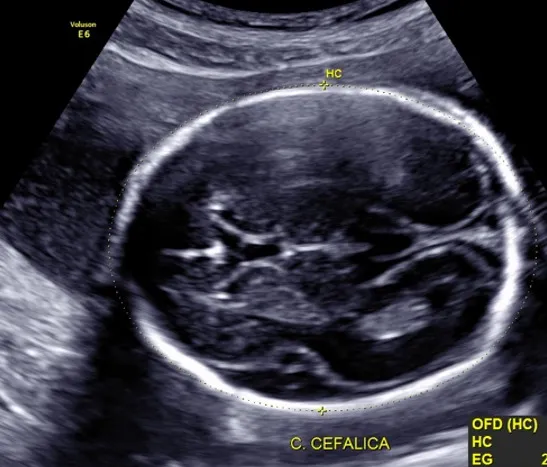

Ultrasonido de crecimiento fetal. (A partir de las 28 semanas).

Este es el tercer estudio importante que se sugiere y los objetivos principales son:

- Evaluar el crecimiento fetal para descartar restricción de crecimiento.

- Valorar líquido amniótico e inserción definitiva de placenta.

- En embarazos complicados se realiza hemodinamia Doppler (flujometría) para conocer el estado de bienestar fetal (que el oxígeno y nutrientes lleguen adecuadamente a bebé a todos los órganos) y evitar resultados perinatales adversos.